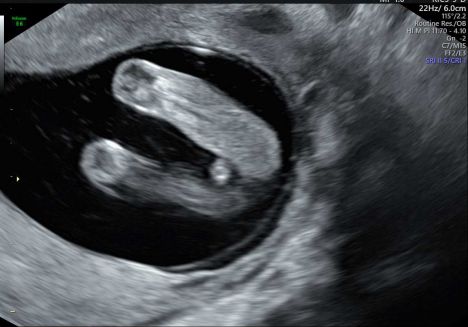

Это девочка?

Да девочка

Определяют по углу наклона в другой проекции. А в такой как у вас у всех еще все одинаково.

У меня с доченькой не было такого ракурса. А вот сейчас в 14 недель врач почти уверена, что сын и у нас иначе этот ракурс выглядит) завтра 16,4 недель, узнаем все ли верно в 14 предположили)

Женя, у меня со старшими мальчиками при том же ракурсе прям по другому было, не могу найти сейчас фото, давно было :)) надеюсь, что в этот раз девочка

Я бы предположила девочку, но возможно рано ещё. Но я думаю девочка

Ну это точно же девочка?  Узнали пол или нет?